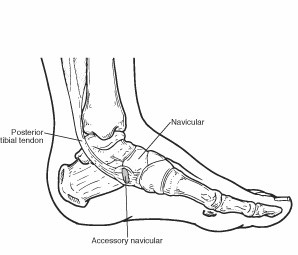

The accessory navicular (os navicularum or os tibiale externum) is an extra bone or piece of cartilage located on the inner side of the foot just above the arch. It is incorporated within the posterior tibial tendon, which attaches in this area.

Many people with accessory navicular syndrome also have flat feet (fallen arches). Having a flat foot puts more strain on the posterior tibial tendon, which can produce inflammation or irritation of the accessory navicular.

- A visible bony prominence on the midfoot (the inner side of the foot, just above the arch)

If nonsurgical treatment fails to relieve the symptoms of accessory navicular syndrome, surgery may be appropriate. Surgery may involve removing the accessory bone, reshaping the area and repairing the posterior tibial tendon to improve its function. This extra bone is not needed for normal foot function.